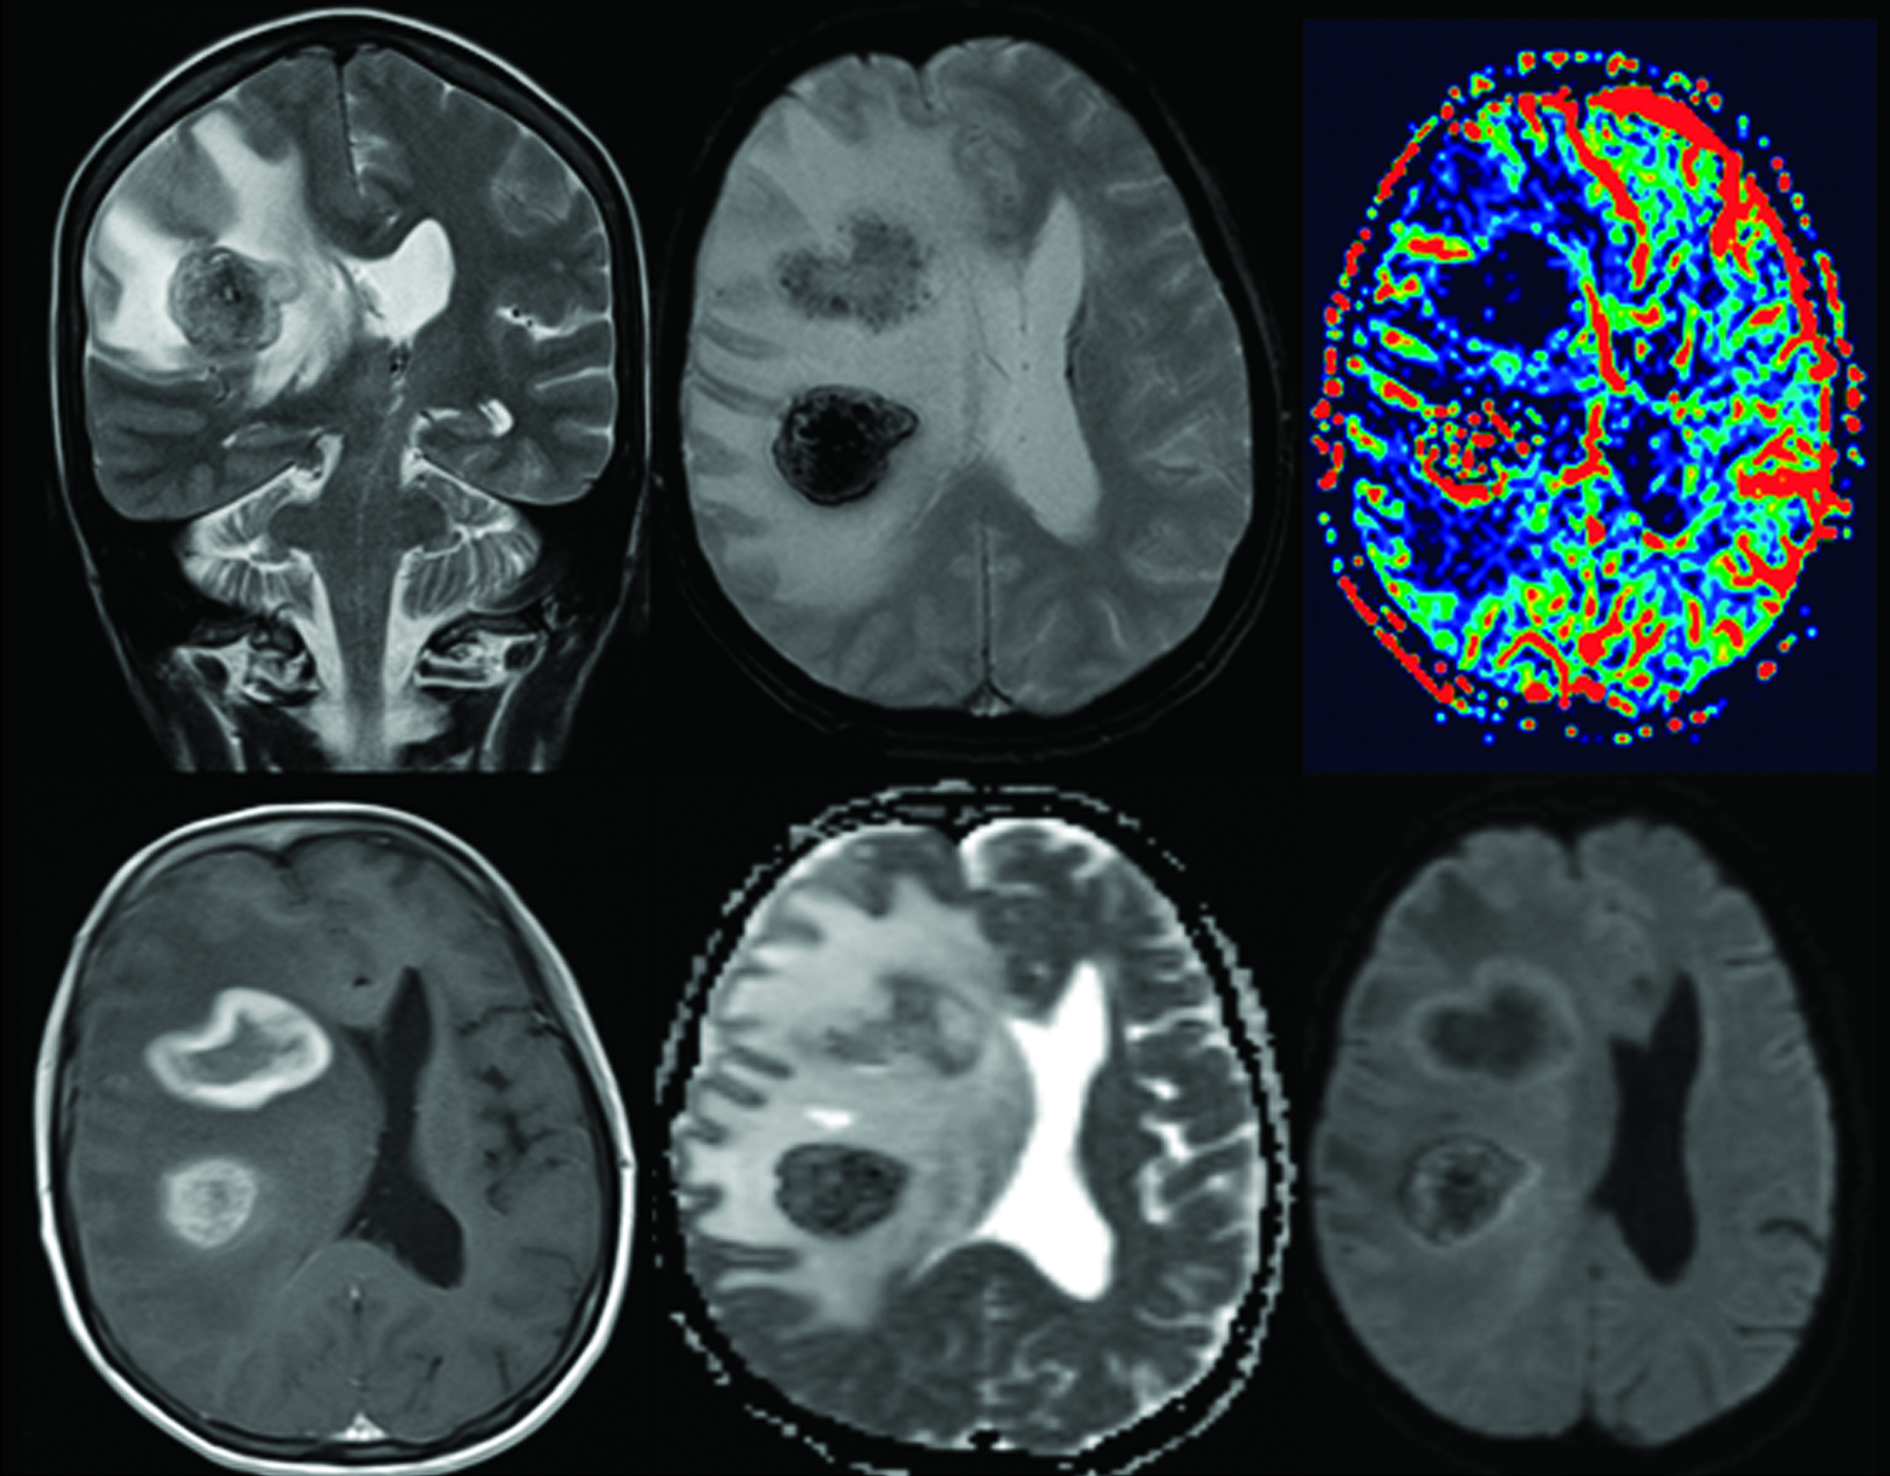

Anatomía Patológica:

En la histología (Fig. 4) se observó una proliferación celular atípica, poco cohesiva, con discreto angiocentrismo y extensas áreas de necrosis. Está compuesta por células de talla grande, bizarras, con citoplasmas eosinófilos, núcleos pleomórficos, en algunos casos adoptando la forma de herradura y otros polilobulados, con nucléolo prominente. Se observaban múltiples mitosis atípicas. Con planteo de neoplasia maligna indiferenciada de alto grado, se realizó un primer panel de inmunohistoquímica, el que mostró positividad intensa y difusa para vimentina y focal para CD45, con negatividad para CK AE1/AE3, Melan A, HMB45 y GFAP, orientando a estirpe linfoide. En un segundo panel se observó positividad intensa, difusa, de membrana y Golgi para CD30, asociado a expresión de CD45RO, CD3, CD4, y EMA focal; TIA-1 y CD38 débiles y focales, mostrando negatividad para CD5, CD8, CD15, CD19, CD138 y ALK. Dichos hallazgos son diagnósticos de compromiso encefálico por un Linfoma de Grandes Células Anaplásico T, ALK negativo.

Figura 4

a) H&E 400x: se observan células de gran talla, pleomórficas, algunas con núcleos en “herradura” y otros polilobulados, asociado a necrosis y hemorragia.

b) Estas células mostraron mediante técnicas de inmunohistoquímica, positividad de membrana para CD30.

c) Positividad citoplasmática para CD3,

d) Negatividad para la proteína ALK.